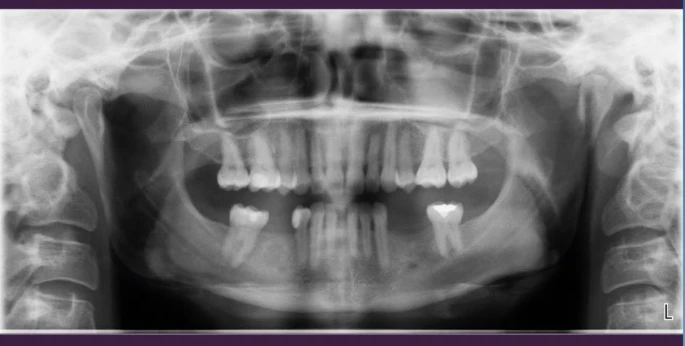

A crown bridge prosthesis in Turkey is a dental restoration used to replace missing teeth by attaching artificial teeth to adjacent natural teeth or implants. The process involves creating a custom bridge that fits into the gap left by the missing tooth, with crowns placed on the adjacent teeth for support. In Turkey, crown bridges prosthesis in turkey are popular for their affordability and quality, as many experienced dentists and advanced dental technology are available at a lower cost compared to Western countries. This procedure can restore both function and aesthetics, providing a natural-looking smile.

A crown bridge prosthesis is used to replace one or more missing teeth, particularly when adjacent teeth are healthy enough to support a bridge. It’s ideal for filling gaps caused by tooth loss due to decay, trauma, or age. A bridge can restore both the function of chewing and the appearance of your smile. It’s often used when a dental implant is not an option or when a more cost-effective solution is preferred. A crown bridge can also help prevent the shifting of remaining teeth, which can lead to further dental issues.